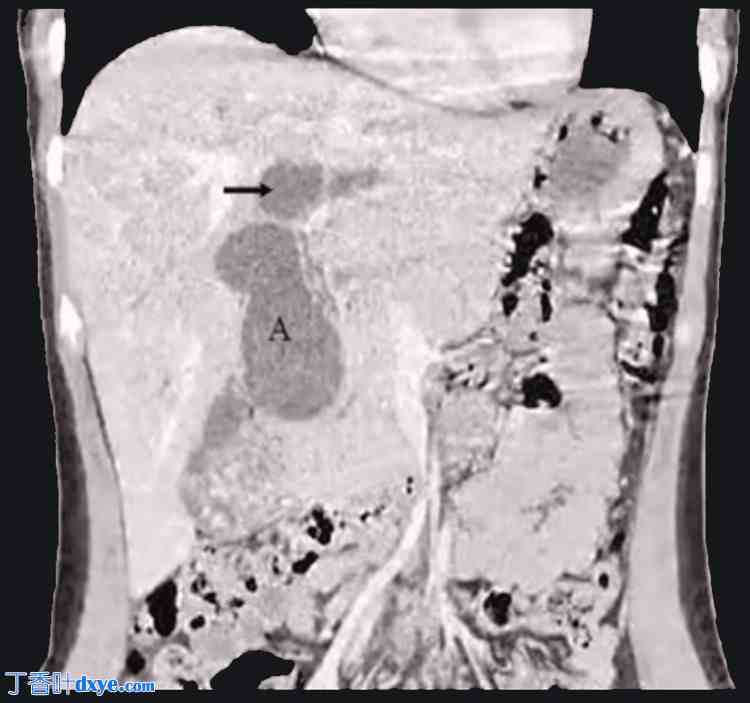

图 2. 增强腹部计算机断层扫描。

该胸腹冠状切面显示肝内外胆管均有明显扩张。从十二指肠上部到肝总管(箭头)均观察到扩张的胆总管 (A),以及左肝管和右肝管。